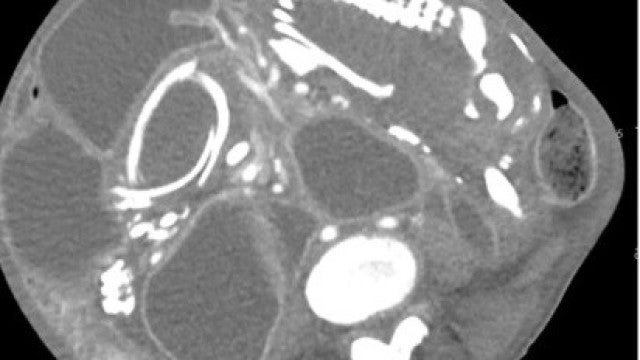

A mulher, cuja identidade não foi revelada, é natural do Congo, mas foi atendida por médicos em Nova York, nos Estados Unidos. Queixava-se de cólicas estomacais, indigestão e um som gorgolejante depois de comer. Era, afinal, um feto calcificado.

A mulher tinha sofrido um aborto há 9 anos e o corpo não tinha expelido o feto. É um caso extremamente raro e há menos de 300 casos documentados. Quando acontece, normalmente deve-se a uma gravidez ectópica, quando o feto não se desenvolve no útero. Por essa mesma razão, o corpo não o conseguiu expelir.

O caso reportado no BMC Women’s Health, revela que o feto comprimia os intestinos.

O feto desenvolveu membros superiores, ossos e até unhas. Seria o nono filho da mulher e parou de se desenvolver pelas 28 semanas.